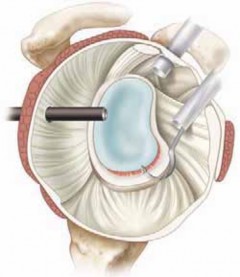

Following the diagnostic sweep, two anterior working portals are established using an outside-in spinal needle localization technique. The anterosuperior portal is typically placed just anterior to the acromioclavicular joint, entering the joint through the rotator interval superior to the biceps tendon; this serves primarily for fluid management and suture retrieval. The critical anteroinferior working portal is placed just superior to the upper border of the subscapularis tendon, ensuring an optimal trajectory (approximately 45 degrees to the glenoid face) for anchor insertion along the anteroinferior glenoid rim. A clear cannula (typically 5.5 mm or 8.25 mm) is introduced to facilitate smooth instrument passage and suture management.

The foundation of a successful arthroscopic stabilization is the meticulous mobilization of the capsulolabral complex. In chronic cases, the torn labrum and IGHL frequently heal in a medially displaced position along the anterior glenoid neck (the ALPSA lesion). Using a combination of arthroscopic elevators, rasps, and electrocautery, the surgeon must aggressively liberate this tissue from the scapular neck. The release must extend inferiorly to the 6 o'clock position to adequately mobilize the inferior capsule. Once the tissue is freed and can be easily reduced to the articular margin, the anterior glenoid neck is lightly decorticated using a motorized burr or rasp. This critical step removes fibrous tissue and exposes bleeding cancellous bone, creating an optimal biological environment for robust soft-tissue healing.

Anchor Placement and Capsulolabral Plication

With the glenoid prepared and the tissue mobilized, fixation begins at the most inferior aspect of the lesion, typically at the 5:30 or 6 o'clock position. Modern fixation relies on either biocomposite or all-suture anchors, typically 1.5 mm to 2.9 mm in diameter. The drill guide is introduced through the anteroinferior portal, and the anchor is deployed on the articular margin (1-2 mm onto the articular cartilage face) to recreate the anatomical labral bumper. The trajectory of the drill is paramount; it must be directed slightly medially to avoid penetrating the articular surface of the glenoid vault.